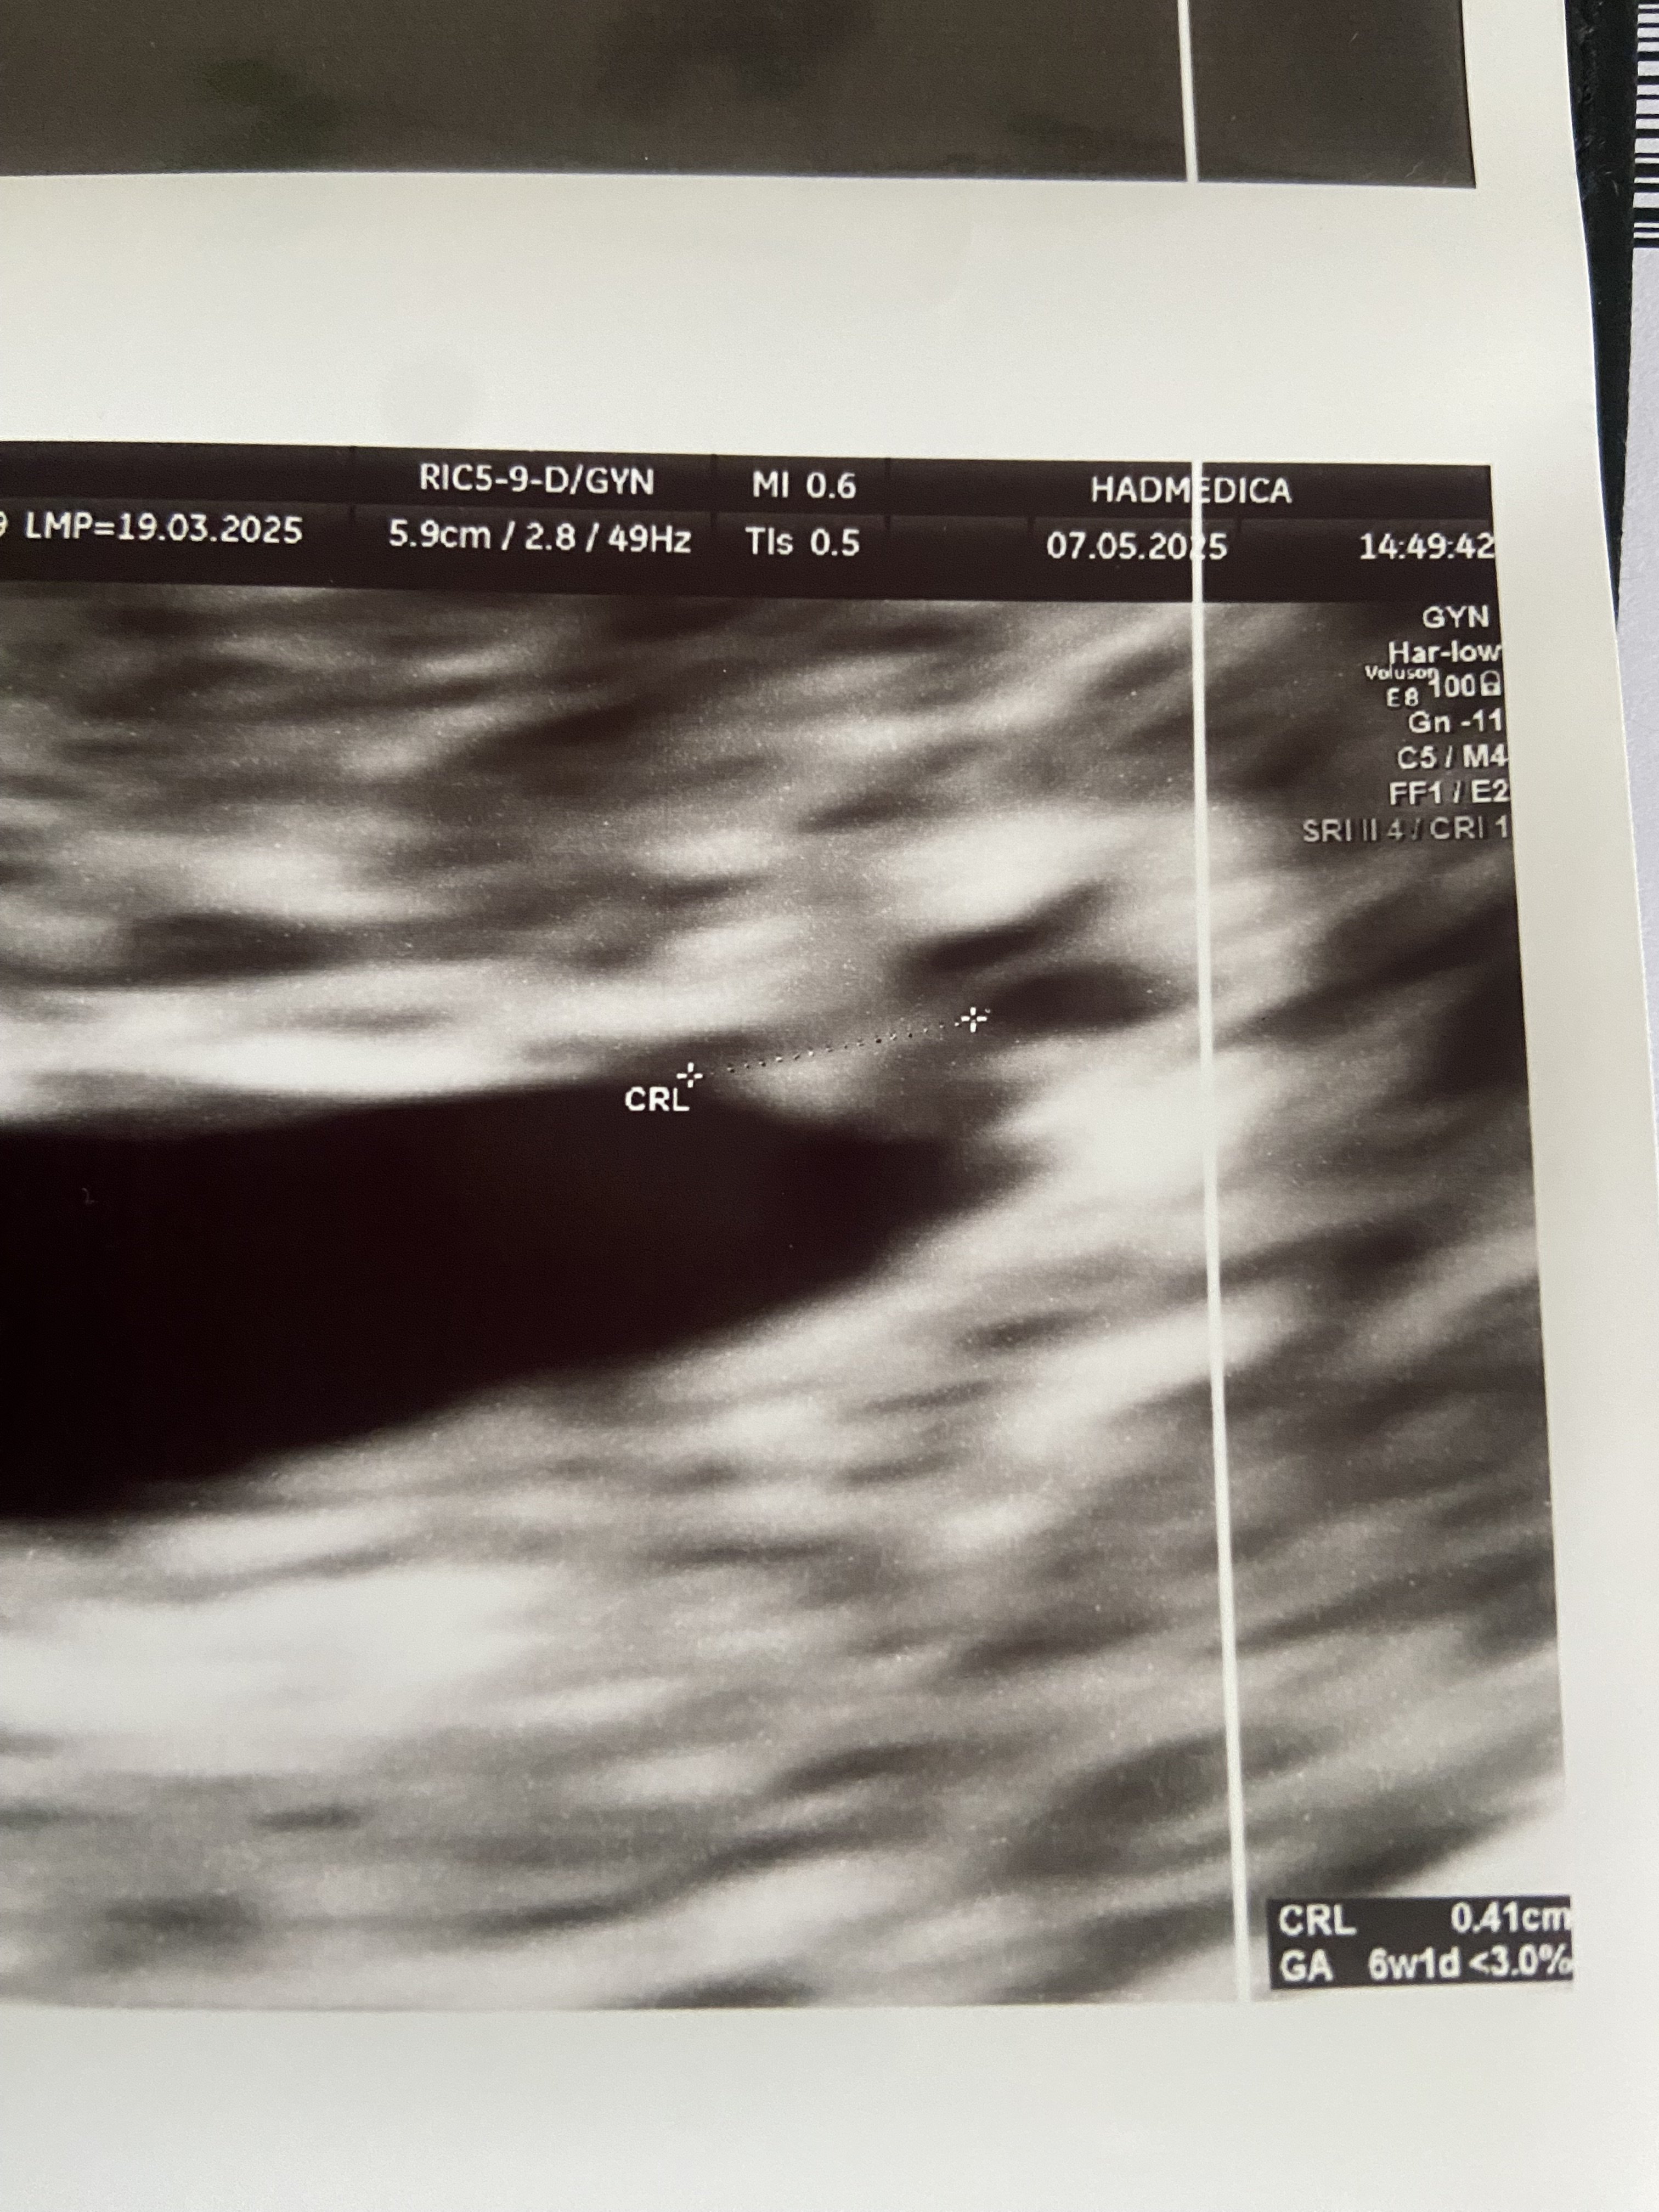

Ja już po wizycie i w pierwszej chwili strach bo pan doktor mówi że nie ma dla mnie dobrych wieści…a za chwilę widzi maleńkie schowane tak że prawie niewidoczne bijące serduszko bpm 86 maleńkie ale szalone bo to dopiero 6t1d. Jestem mega szczęśliwa bo widziałam te maleńkie bijące serduszko. Następna wizyta 21.05 i zobaczymy czy będzie nadal wszystko ok. Dziękuję za wsparcie i proszę o więcej bo to dopiero początek naszej historii 😘😘😘😘😘😘😘😘😘😘😘😘😘😘😘😘😘😘